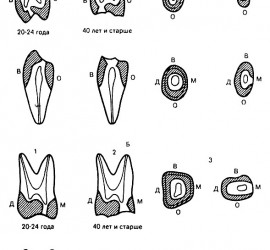

Жевательная проба. Критерий оценки эффективности работы жевательного аппарата, которую определяют по 3 показателям: жевательная эффективность, жевательный эффект и жевательная способность. Тестовым материалом для жевательной пробы могут служить пищевые продукты (орехи, морковь, хлеб) и искусственно созданные (20% желатина, отвержденная в 4% формалине, ортосил, другие пластмассы). Обязательным условием для воспроизводимости результатов пробы […]